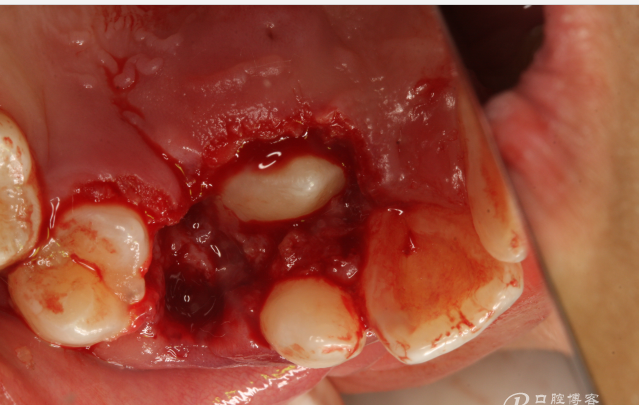

圖9.清理切除部分腭側(cè)組織后的13牙冠。

圖10.拔除右側(cè)乳尖牙

圖11.從乳尖牙到13牙冠區(qū)域去皮質(zhì)骨化處理